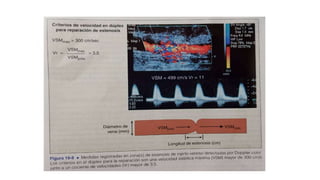

Calculo de la velocidad de flujo media en el injerto:

Calculo de lavelocidad de flujo media en el injerto: